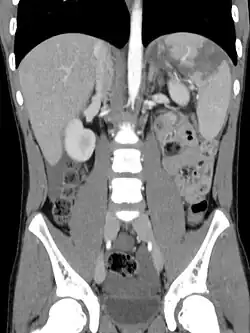

Die apparative Basisdiagnostik bei einem Verdacht auf Milzruptur ist die Sonographie der Bauchorgane. Der Nachweis von freier Flüssigkeit gelingt damit bereits bei kleinen Mengen, gröbere Parenchymverletzungen der Milz oder große subkapsuläre Hämatome lassen sich ebenfalls darstellen. Bei unauffälligem sonographischem Befund aber klinisch weiter bestehendem Verdacht muss die Untersuchung engmaschig wiederholt werden, um eine zweizeitige Ruptur oder ein zunehmendes Kapselhämatom nicht zu übersehen. Röntgenaufnahmen des Thorax und des Abdomens erbringen keine weiteren Hinweise auf das Vorliegen einer Milzruptur, werden aber zum Ausschluss weiterer Verletzungen (beispielsweise Rippenfrakturen mit Pneumothorax) durchgeführt. Bei stabilen Kreislaufverhältnissen kann eine Computertomographie des Abdomens genaueren Überblick über das Ausmaß der Milzverletzung geben. Die noch bis in die 1990er Jahre regelmäßig durchgeführte Peritoneallavage ist mittlerweile wegen ihrer hohen Fehlerquote nicht mehr gebräuchlich.